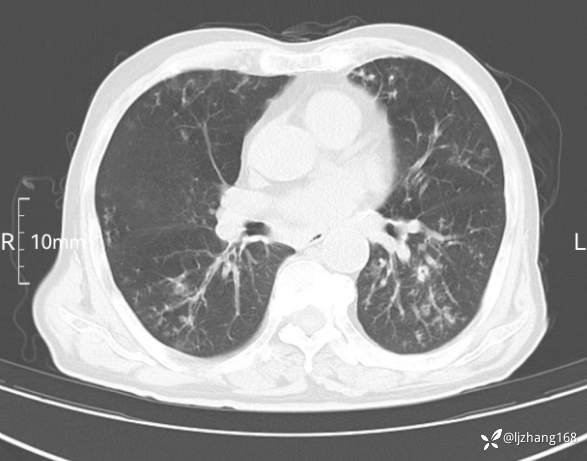

老年男患,咳嗽,气短,双肺多发间质性病变,何种感染?(有结果)

辅助检查:胸部CT:双肺肺气肿,间质性病变,血气分析:PH 7.413, PCO2 29.2mmHg, PO2,81.8mmHg,乳酸 3.3mmol/1,剩余碱-4.0mmol/1,HC03 18.8mmol/1。全血超敏C反应蛋白:超敏C反应蛋白 135.60 mg/L、 白细胞 14x19^9/L,中性粒细胞11.6x10^9/L。